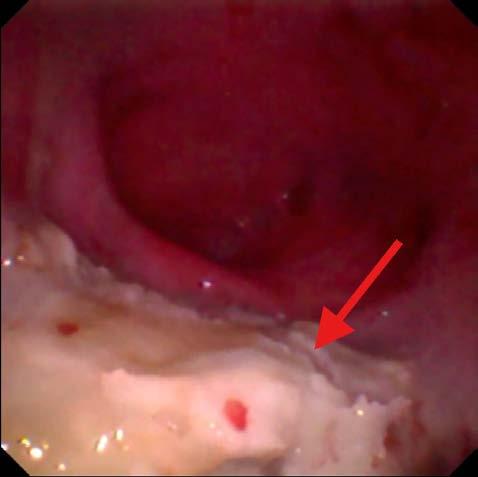

Se procedió a realizar una TC de cráneo (posicionamiento en recumbencia esternal, con 1,25 mm de corte, adquiriendo imágenes pre y postcontraste con contraste yodado Iohexol (Omnipaque 300 mg/ ml, GE Healthcare Bio-Sciences, Florida) 400 mg/kg, con algoritmo de reconstrucción de tejido blando y hueso, General Electrics Healthcare, 4 cortes, España, Madrid). En la TC se observó en la cavidad nasal izquierda una moderada destrucción de turbinetes nasales con severo engrosamiento de la mucosa nasal y presencia de tejido blando anómalo (Fig. 1A), sin presencia de masas o cuerpos extraños, ni afectación de la lámina cribiforme. Dichas lesiones se extendían al seno frontal izquierdo (Fig. 1B). A continuación, se realizó una rinoscopia (fibroscopio 5,9 mm, FujiFilm, España, Madrid) donde se observó en la cavidad nasal izquierda múltiples placas de color blanquecino con aspecto caseoso/algodonoso adheridas a la mucosa nasal con eritema y congestión asociados (Fig. 2), junto a la destrucción moderada de los turbinetes, mostrando un aspecto cavitado. La cavidad nasal derecha no presentó alteraciones. Se tomaron muestras de tejido (placa fúngica y mucosa adyacente) para cultivo y análisis histopatológico. En el cultivo se obtuvo un crecimiento de Aspergillus fumigatus, y en los resultados de la biopsia de la placa fúngica se observó un tejido eosinofílico con abundantes hifas septadas, mientras que en el tejido adyacente se evidenció una mucosa erosionada y ulcerada con abundantes neutrófilos y macrófagos con hifas fúngicas esporádicas. Como terapia se optó por la aplicación tópica intranasal de una pomada depot de clotrimazol 1 %

Tras el primer tratamiento los signos clínicos se mantuvieron, por lo que se realizó una segunda rinoscopia a las 3 semanas, observándose una mejoría respecto a la anterior, pero aún presentaba pequeñas placas fúngicas (Fig. 4).

Dada la afección del seno frontal izquierdo se realizó una trepanación para poder acceder con el fibroscopio, evidenciando placas de gran tamaño en el seno izquierdo (Fig. 5). Se volvió a realizar el mismo procedimiento de desbridamiento y lavado de las placas de la cavidad nasal junto al de las placas del seno (a través de los orificios realizados); posteriormente, se aplicó una suspensión líquida de enilconazol 2 % (fórmula magistral 200 mg/ml, Valencia) mediante sondas introducidas en los senos y los orificios nasales, taponando las narinas y la nasofaringe mediante sondas Foley (MILA international Inc, Kentucky, EE. UU.) hasta ocupar toda la cavidad nasal y senos, manteniéndola durante 15 minutos. Tras ello, se drenó por gravedad mediante la retirada de las sondas Foley y colocación de la cabeza en posición declive. Finalmente, se aplicó una crema depot de clotrimazol 1 % a través de las sondas, ocupando los senos y el tejido de la cavidad

3. Aspecto tras el desbridamiento de la cavidad nasal izquierda (meato nasal), con ausencia del laberinto etmoidal. La mucosa presenta un aspecto eritematoso con focos de sangrado tras el proceso.